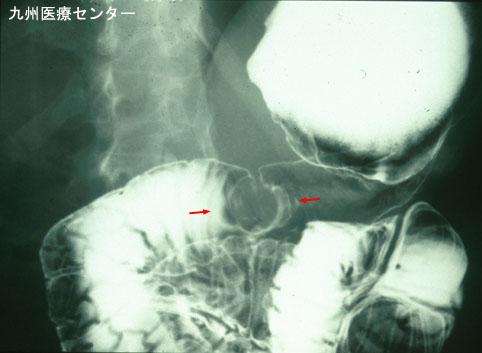

症例提示(所在地,施設名等): 福岡県・ 九州医療センター

疾患(病理主体)の分類悪性上皮性腫瘍/腺癌

部位(臓器別)十二指腸/下行脚

検査方法X-P

腫瘍の肉眼分類0型(表在型)/I型(Ip)

病変の最大径(ミリ)25〜29

腫瘍の深達度sm